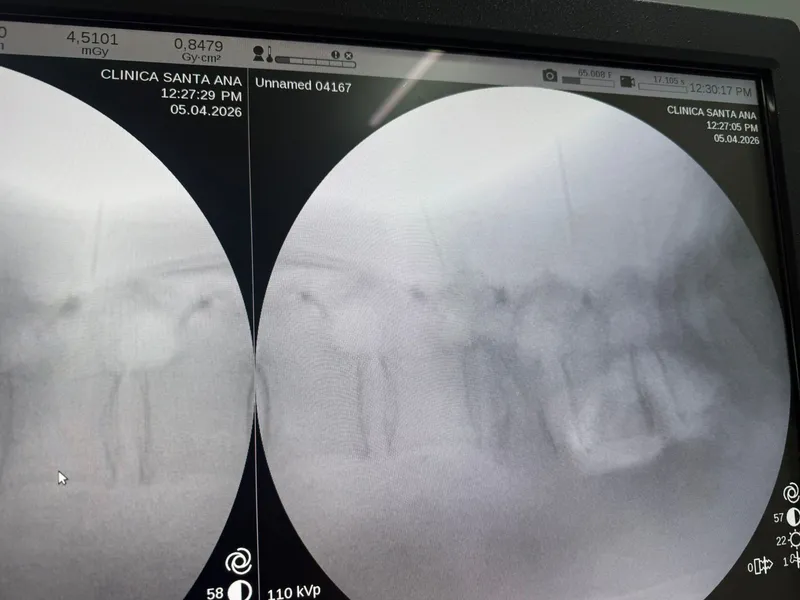

Control con Fluoroscopia: Precisión en Cada Tornillo

Uno de los elementos clave de esta cirugía es el control fluoroscópico intraoperatorio. En cada paso, se verificó con rayos X en tiempo real que los tornillos estuvieran correctamente posicionados dentro de los pedículos, sin comprometer el canal medular ni las raíces nerviosas.

Las imágenes fluoroscópicas confirmaron la correcta colocación de todos los tornillos pediculares con distribución simétrica y adecuada penetración en los cuerpos vertebrales, junto con buen volumen de cemento alrededor de cada tornillo.